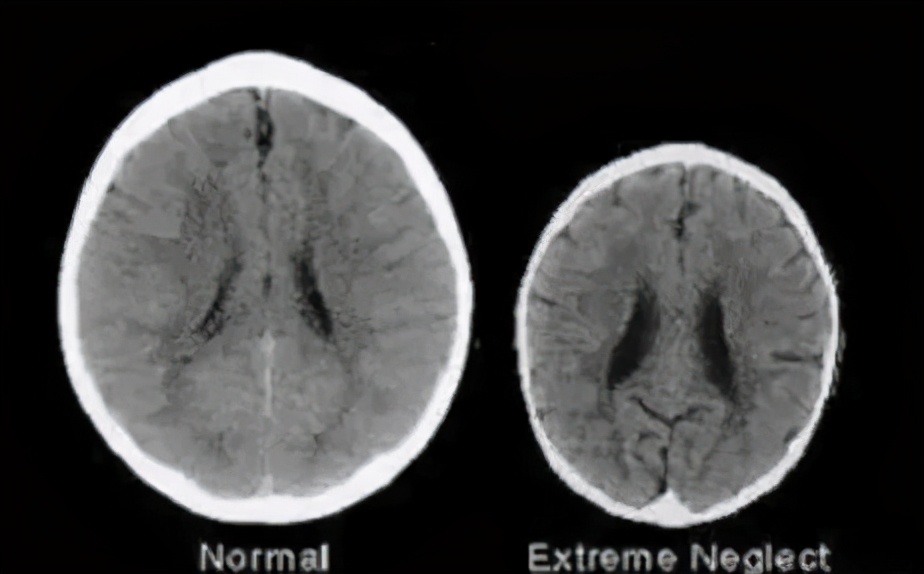

后来又有人找了两个3岁的孩子做了一次大脑扫描。

2个孩子同龄、同性别、家境也类似,唯一不同的是,一个孩子经常被夸,一个经常被骂。

结果,他们的大脑扫描图,竟出现天壤之别。